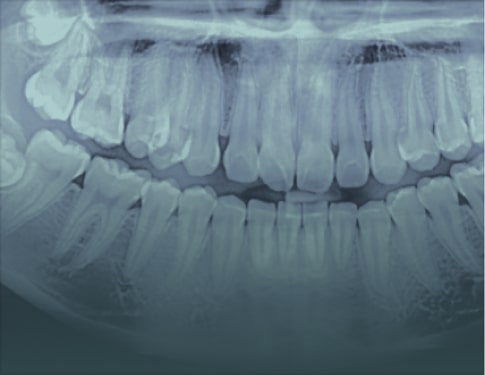

Screening Report is a concise, text-only summary designed for straightforward cases or when you simply need to rule out pathology. This option is often used when an image was taken for a specific purpose, but you’d like a radiologist to review the entire scan as part of our dental teleradiology services, confirming there are no incidental findings across the full set of medical images.

Advanced Report includes annotated images, detailed key findings, and practical clinical recommendations. Choose this option for treatment planning, complex cases, referrals, or when visuals are needed to communicate findings with colleagues or patients and support confident clinical decisions in the final report.